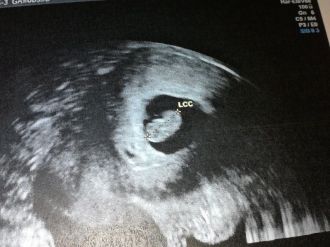

écho 1er trimestre

Oufff tout va bien je suis trop heureuse en fin je peux dire je suis enceinte!! avec le papa on a déja un pronostic pour le sexe je vous met une foto puis une otre aprè dites moi ce que vous en pensez!! donc la dpa est pour le 10 novembre!!après l'écho direction labo pour faire la pds pour la trisomie et les magasins pour acheter un petit truc je vous met aussi la foto ensuite!!

Message déposé le 25.04.2013 à 10:38 - Commentaires (5)

écho datation

Voila hier j'ai eu mon écho de datation donc tout va bien le petit bout fait 13.87mm et donc la date a changé ce serait pour le 13 novembre maintenant!!

Message déposé le 26.03.2013 à 11:24 - Commentaires (5)